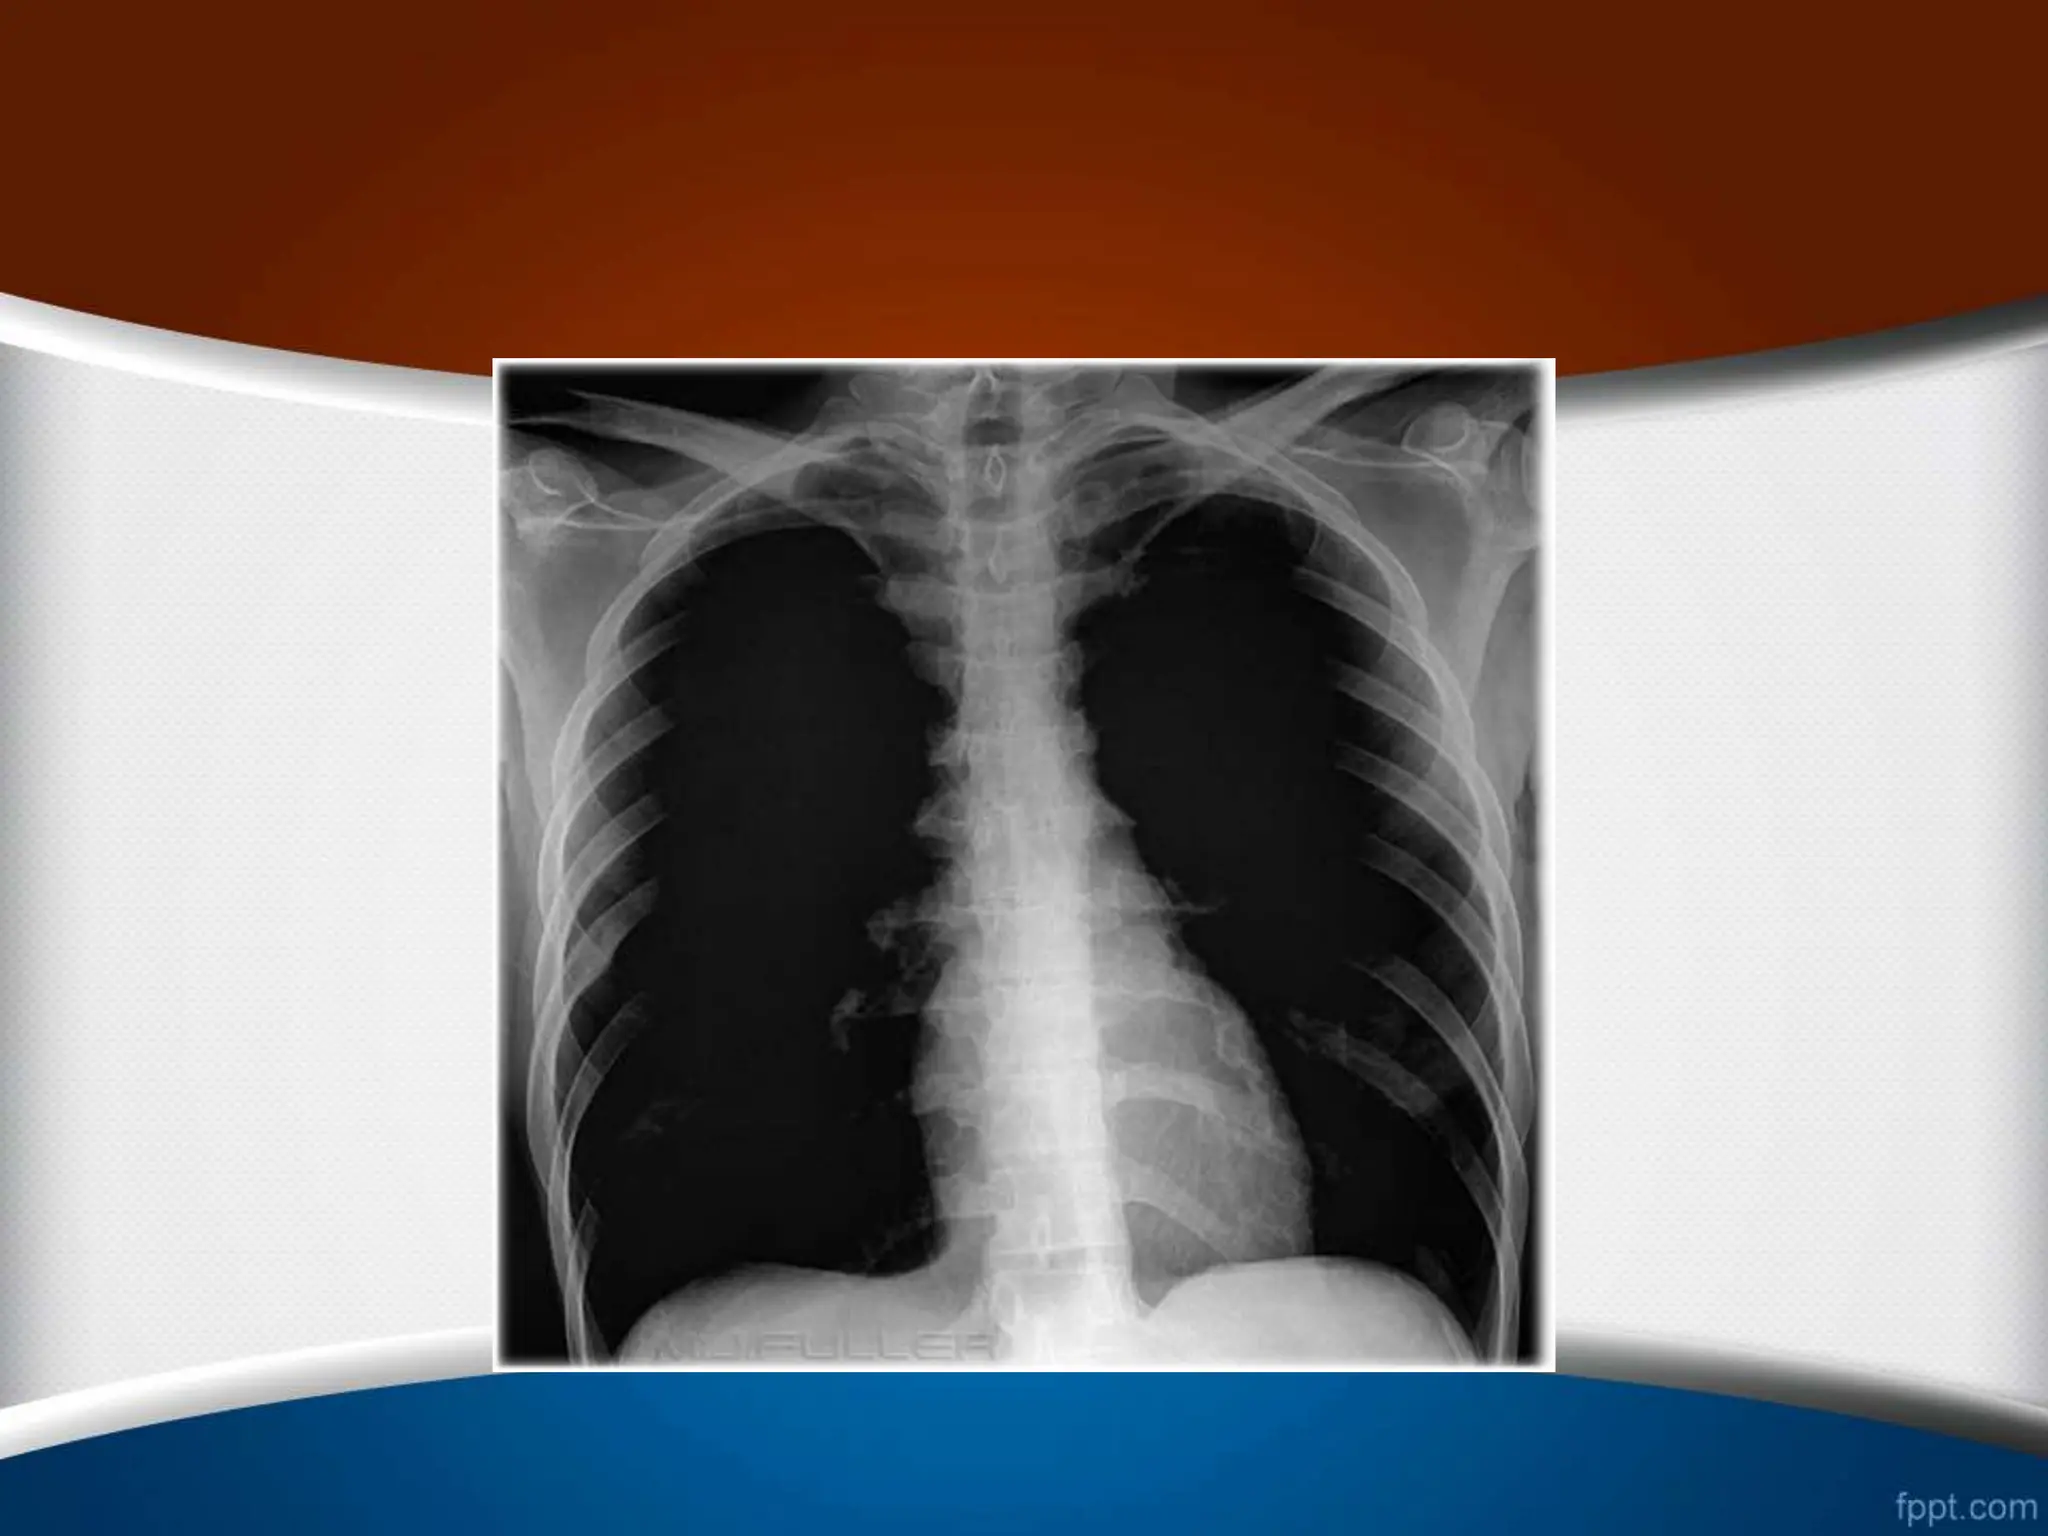

Exposure ‫قرار‬ ‫اشعه‬ ‫معرض‬ ‫در‬ ‫میزان‬ ‫یا‬

‫دنده‬ ‫و‬ ‫ریوی‬ ‫عروق‬ ،‫فقرات‬ ‫ستون‬ ‫مشاهده‬

‫نشان‬ ‫قلب‬ ‫پشت‬ ‫از‬ ‫ها‬

‫است‬ ‫اشعه‬ ‫میزان‬ ‫بودن‬ ‫مناسب‬

.

2

-

‫ریوی‬ ‫عروق‬ ‫اما‬ ،‫شود‬ ‫مشاهده‬ ‫فقرات‬ ‫ستون‬ ‫فقط‬ ‫که‬ ‫صورتی‬ ‫در‬

‫است‬ ‫تاریک‬ ‫فیلم‬ ‫نشود‬ ‫مشاهده‬

(Over exposure)

3

‫سفی‬ ‫خیلی‬ ‫فیلم‬ ،‫نشود‬ ‫مشاهده‬ ‫فقرات‬ ‫ستون‬ ‫که‬ ‫صورتی‬ ‫در‬

‫د‬

‫است‬

(Under exposure)